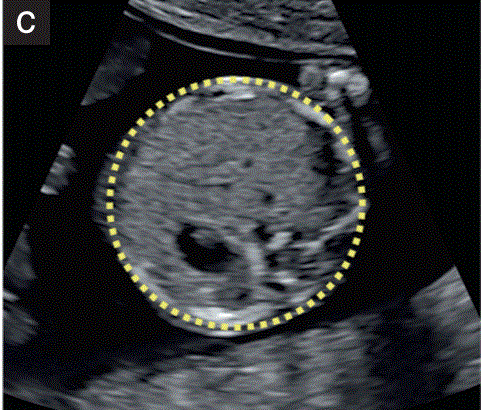

腹围的测量(AC)

AC的测量是在胎儿腹部的横断切面上进行的。在胃部可见的位置(图1-c)。在皮肤线的外表面。

它可以直接用椭圆游标测量,也可以通过垂直的线性测量计算,通常是前后腹部直径(APAD)和TAD。

为了测量APAD,卡尺被放置在身体轮廓的外部边界上,从背部(覆盖脊柱的皮肤)到腹部前壁。

为了测量TAD,卡尺被放置在身体轮廓的外边缘,在腹部最宽的地方。

AC可使用以下公式计算:AC π(APAD TAD)/2 1.57 (APAD TAD).

进行这种测量的一个优点是,用于记录它的图像还显示了胃的位置。

图1 11+0至14+0周胎儿超声检查可获得的测量值。(c) 胎儿上腹部的横断切面。显示腹围的测量。注意腹腔气泡和脐静脉的存在,脊柱横切面在三点钟位置, 每侧可见一根肋骨。在这个平面上不应该看到胎儿的肾脏。